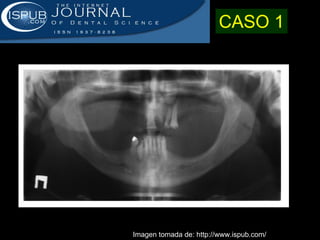

Este documento describe la acromegalia, una condición causada por un exceso de hormona de crecimiento producida por la hipófisis. Provoca un crecimiento anormal de las extremidades, la cara y los órganos internos. Sus síntomas incluyen prominencia de la mandíbula, las manos y los pies, así como engrosamiento de la piel y huesos. Generalmente se debe a un adenoma de la hipófisis y su diagnóstico se realiza mediante pruebas de sangre y resonancia magnética.